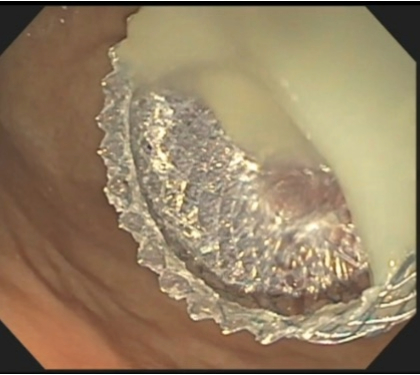

The study, which ran from November 2019 to October 2022, analyzed the benefits of endoscopic interventions to determine the optimal treatment strategy in patients with infected necrotizing pancreatitis. The single-blind randomized trial included 70 patients and compared the outcomes between performing upfront necrosectomy at index intervention versus step-up approach.

The clinical trial provided high-level evidence to substantiate the treatment approach that in stabilized patients with infected necrotizing pancreatitis and well demarcated collections, performing endoscopic necrosectomy at index treatment session resulted in numerous benefits. These included an early resolution of systemic inflammation and organ failure, less reinterventions, shorter lengths of hospital stay and lower costs as compared to step-up approach.

“We concluded that necrosectomy performed the first day the stent is placed decreases the number of interventions with no increase to risk,” says Dr. Varadarajulu. “We believe the outcome of this trial will likely result in a shift to upfront necrosectomy as the treatment preference.”